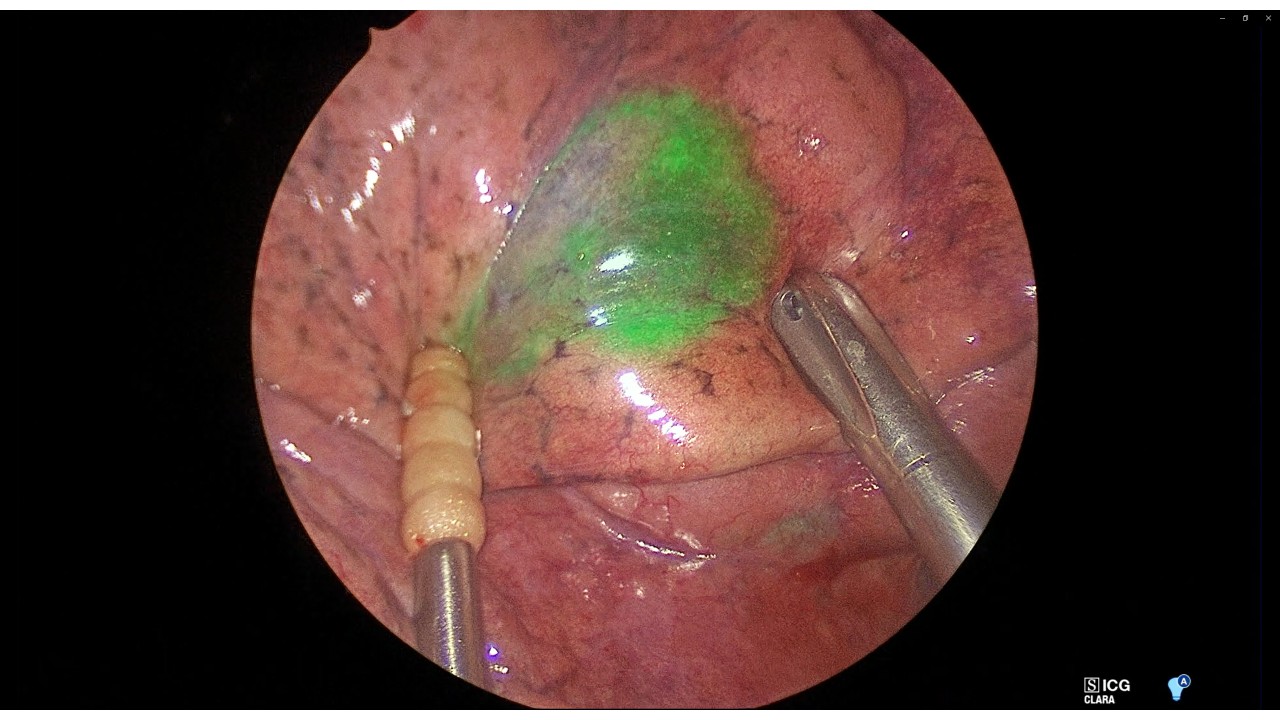

- 当科では蛍光色素によるCTガイド肺マーキング法(ICGオーバーレイ法)を考案し多く実施してきた(図右上)。本法は合併症がほぼなく安全に実施でき、明瞭な発光として病変位置を同定でき(図中)、病変位置が大変わかりやすい。この技術によって胸腔鏡やロボットによる正確な肺部分切除・肺区域切除を行うことができる。当科の得意とするところである。

- このマーキングと肺血管気管支構造(図下)とを組み合わせることで、切除範囲を立体的にイメージし精緻な手術を行っている。